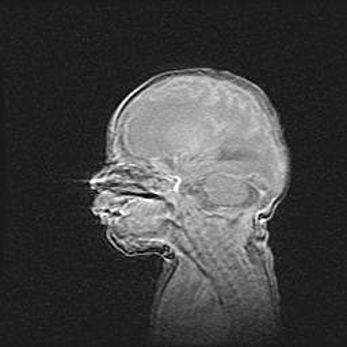

Подострая гематома правой гемисферы мозжечка.

Наружная гидроцефалия.

Возраст: 15 дней

Вес: 3100 г

Пол: женский

Окружность головы: 37 см

Срок гестации: 35-36 недель

При открытой наружной форме гидроцефалии у новорожденных расширяются и переполняются субарахноидные пространства.

Кровоизлияния в мозжечок имеют две клинико-анатомические формы: полушарные гематомы и кровоизлияния в червь.

К появлению этой патологии может привести: повреждения головного мозга, возникающие в результате асфиксии и гипоксии плода при беременности, или травмы во время родов. Редко гематома мозжечка может быть результатом первичной коагулопатии и сосудистой мальформации, диссеминированном внутрисосудистом свертывании, изоиммунной тромбоцитопении.